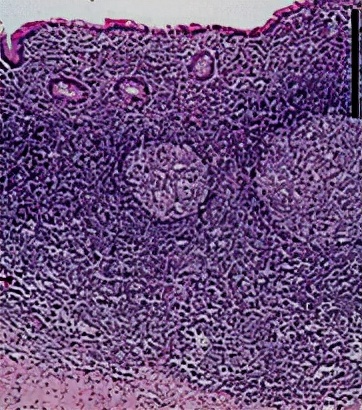

(二)病因和病理类型 1.病因 (1) 阑尾管腔阻塞:淋巴滤泡增生 、粪石、异物、肿瘤等。 (2)细菌入侵:G-杆菌及厌氧菌。 (3) 阑尾先天畸形。

2.病理类型

1.急性单纯性阑尾炎 |

各层水肿和中性粒细胞浸润,黏膜表面小溃疡和出血点 |

阑尾管腔阻塞 |

2.急性化脓性阑尾炎 |

脓性渗出物附着 |

炎症加重 |

3.坏疽性及穿孔性阑尾炎 |

阑尾管壁坏死或部分坏死,呈紫黑色或黑色 |

加剧可发生穿孔 |

*阑尾周围脓肿 |

化脓坏疽时,大网膜移至右下腹,将阑尾包裹并形成粘连 |

形成炎性包块或阑尾周围脓肿 |